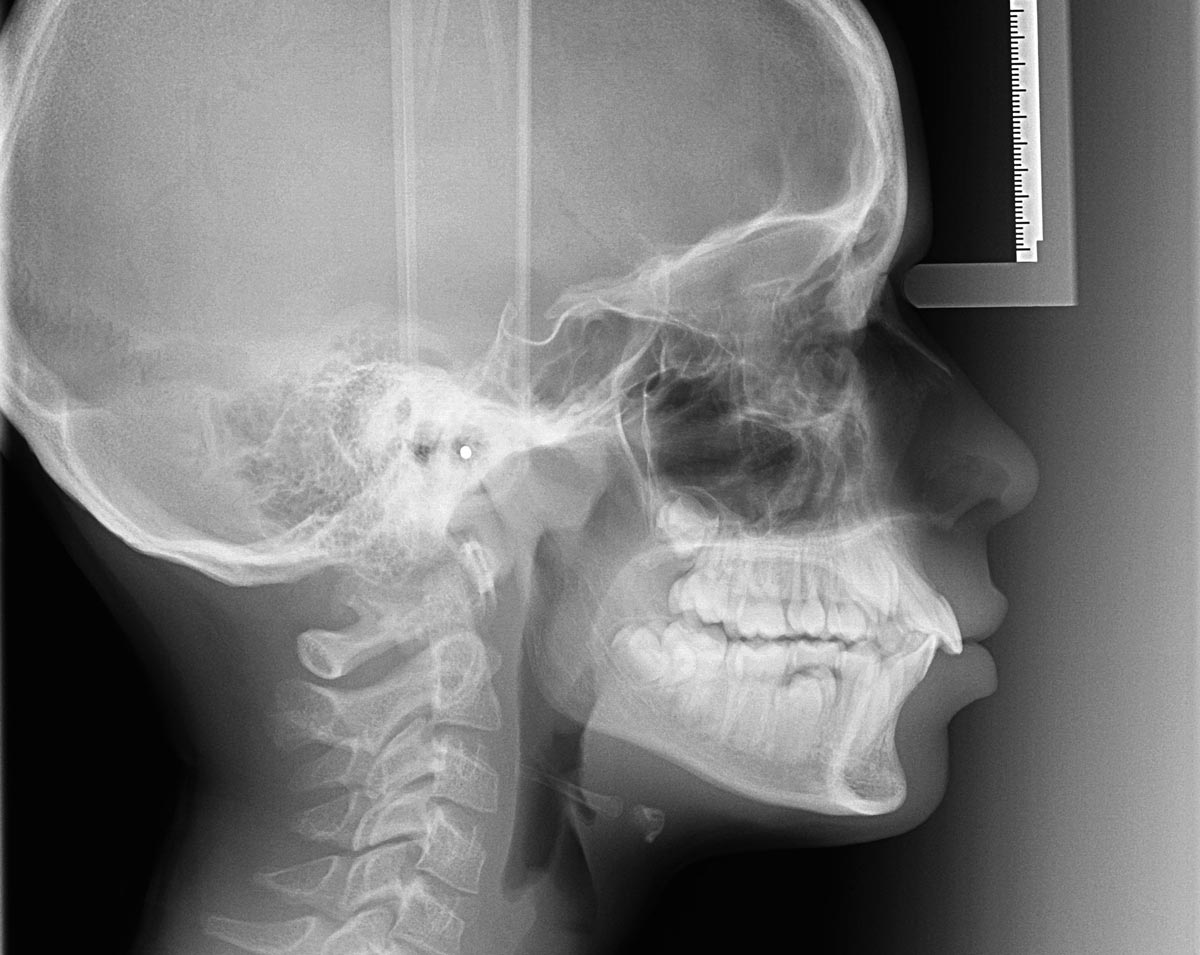

Il termine ortodonzia deriva e etimologicamente dal greco antico e significa letteralmente dentatura dritta, è quella branca dell’odontoiatria che si occupa della cura dei rapporti anomali esistenti tra le arcate dentarie e tra le strutture anatomiche ad esse correlate: sistema nervoso centrale, muscolatura facciale masticatoria e componenti scheletriche.

L’apparecchio ortodontico è necessario per prevenire o per risolvere tutta una serie di disturbi che interessano le gengive, la masticazione, la colonna vertebrale, le articolazioni, i muscoli e l’apparato maxillo-facciale (denti, mandibola e mascelle) e possono causare cefalea muscolo-tensiva e mal di collo.